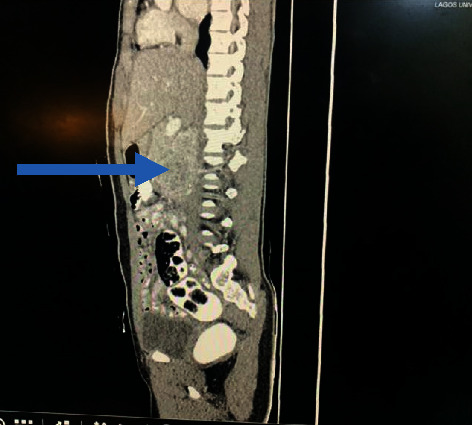

Introduction: A paraganglioma (PGL) is a tumour derived from extra-adrenal chromaffin cells of the sympathetic paravertebral ganglia of the thorax, abdomen, and pelvis. Cardiovascular manifestations predominate but neurological symptoms like seizures can occur requiring a high index of suspicion for prompt diagnosis and treatment. Case Description. A 14-year-old girl was referred to the paediatric neurology unit for recurrent headaches of one-year duration, vomiting of 2 months duration, and an episode of generalized tonic-clonic seizures, 2 weeks prior to presentation. There was an associated history of impaired vision, palpitations, diaphoresis, and easy fatigability. Her blood pressure ranged from 150/101 to 160/120 mmHg. The brain CT scan was normal. ECG showed left ventricular hypertrophy. Abdominal USS revealed a right para-aortic mass necessitating 24-hour urine normetanephrine which was markedly elevated-1695.34 mcg/24 h (100-500). An abdominal CT scan confirmed a paraganglioma in the right para-aortic region. A multidisciplinary team consisting of paediatric endocrinologists, radiologists, anaesthetists, paediatric and cardiothoracic surgeons, and the intensive care unit (ICU) team was involved in the peri and postoperative management of the child. Intraoperative challenges were hypertension and hypotension (following tumour excision). She was nursed in the ICU for 48 hours. Histology results confirmed paraganglioma. Postoperative urine normetanephrines done a month after surgery had reverted to normal. Her blood pressure has remained normal 6 months after surgery, and no other symptoms have recurred.

Abstract Image